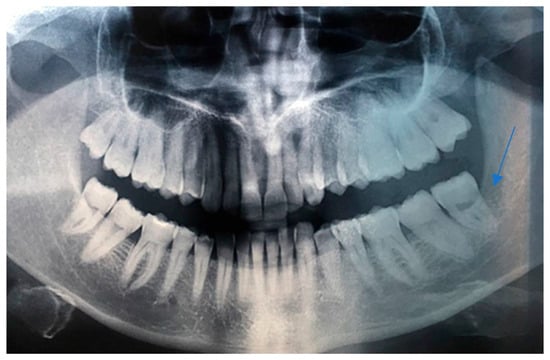

Postoperative management included close clinical and radiographic follow-up to monitor healing and detect possible recurrence. Unfortunately, postoperative photographic documentation was initially incomplete because the patient moved to another city shortly after surgery and continued follow-up at a different institution. However, we were able to obtain a postoperative clinical photograph taken a few months prior to her death, as well as postoperative radiographic imaging, which confirm satisfactory healing of the surgical site (Figure 8 and Figure 9). Approximately two years after surgery, the patient passed away due to cardiovascular complications unrelated to the oral neoplasm. Her death occurred after the initial diagnostic and therapeutic course, limiting further evaluation of the lesion’s long-term outcome and response to treatment.

Figure 8.

Twenty-two-month postoperative follow-up demonstrating satisfactory mucosal healing with no evidence of local recurrence.

Figure 9.

Postoperative radiographic and MRI composite images showing complete removal of the lesion and extraction of the involved teeth (3.7 and 3.8). No evidence of radiolucency or residual mass is observed in the surgical area, confirming adequate bone healing and absence of recurrence.